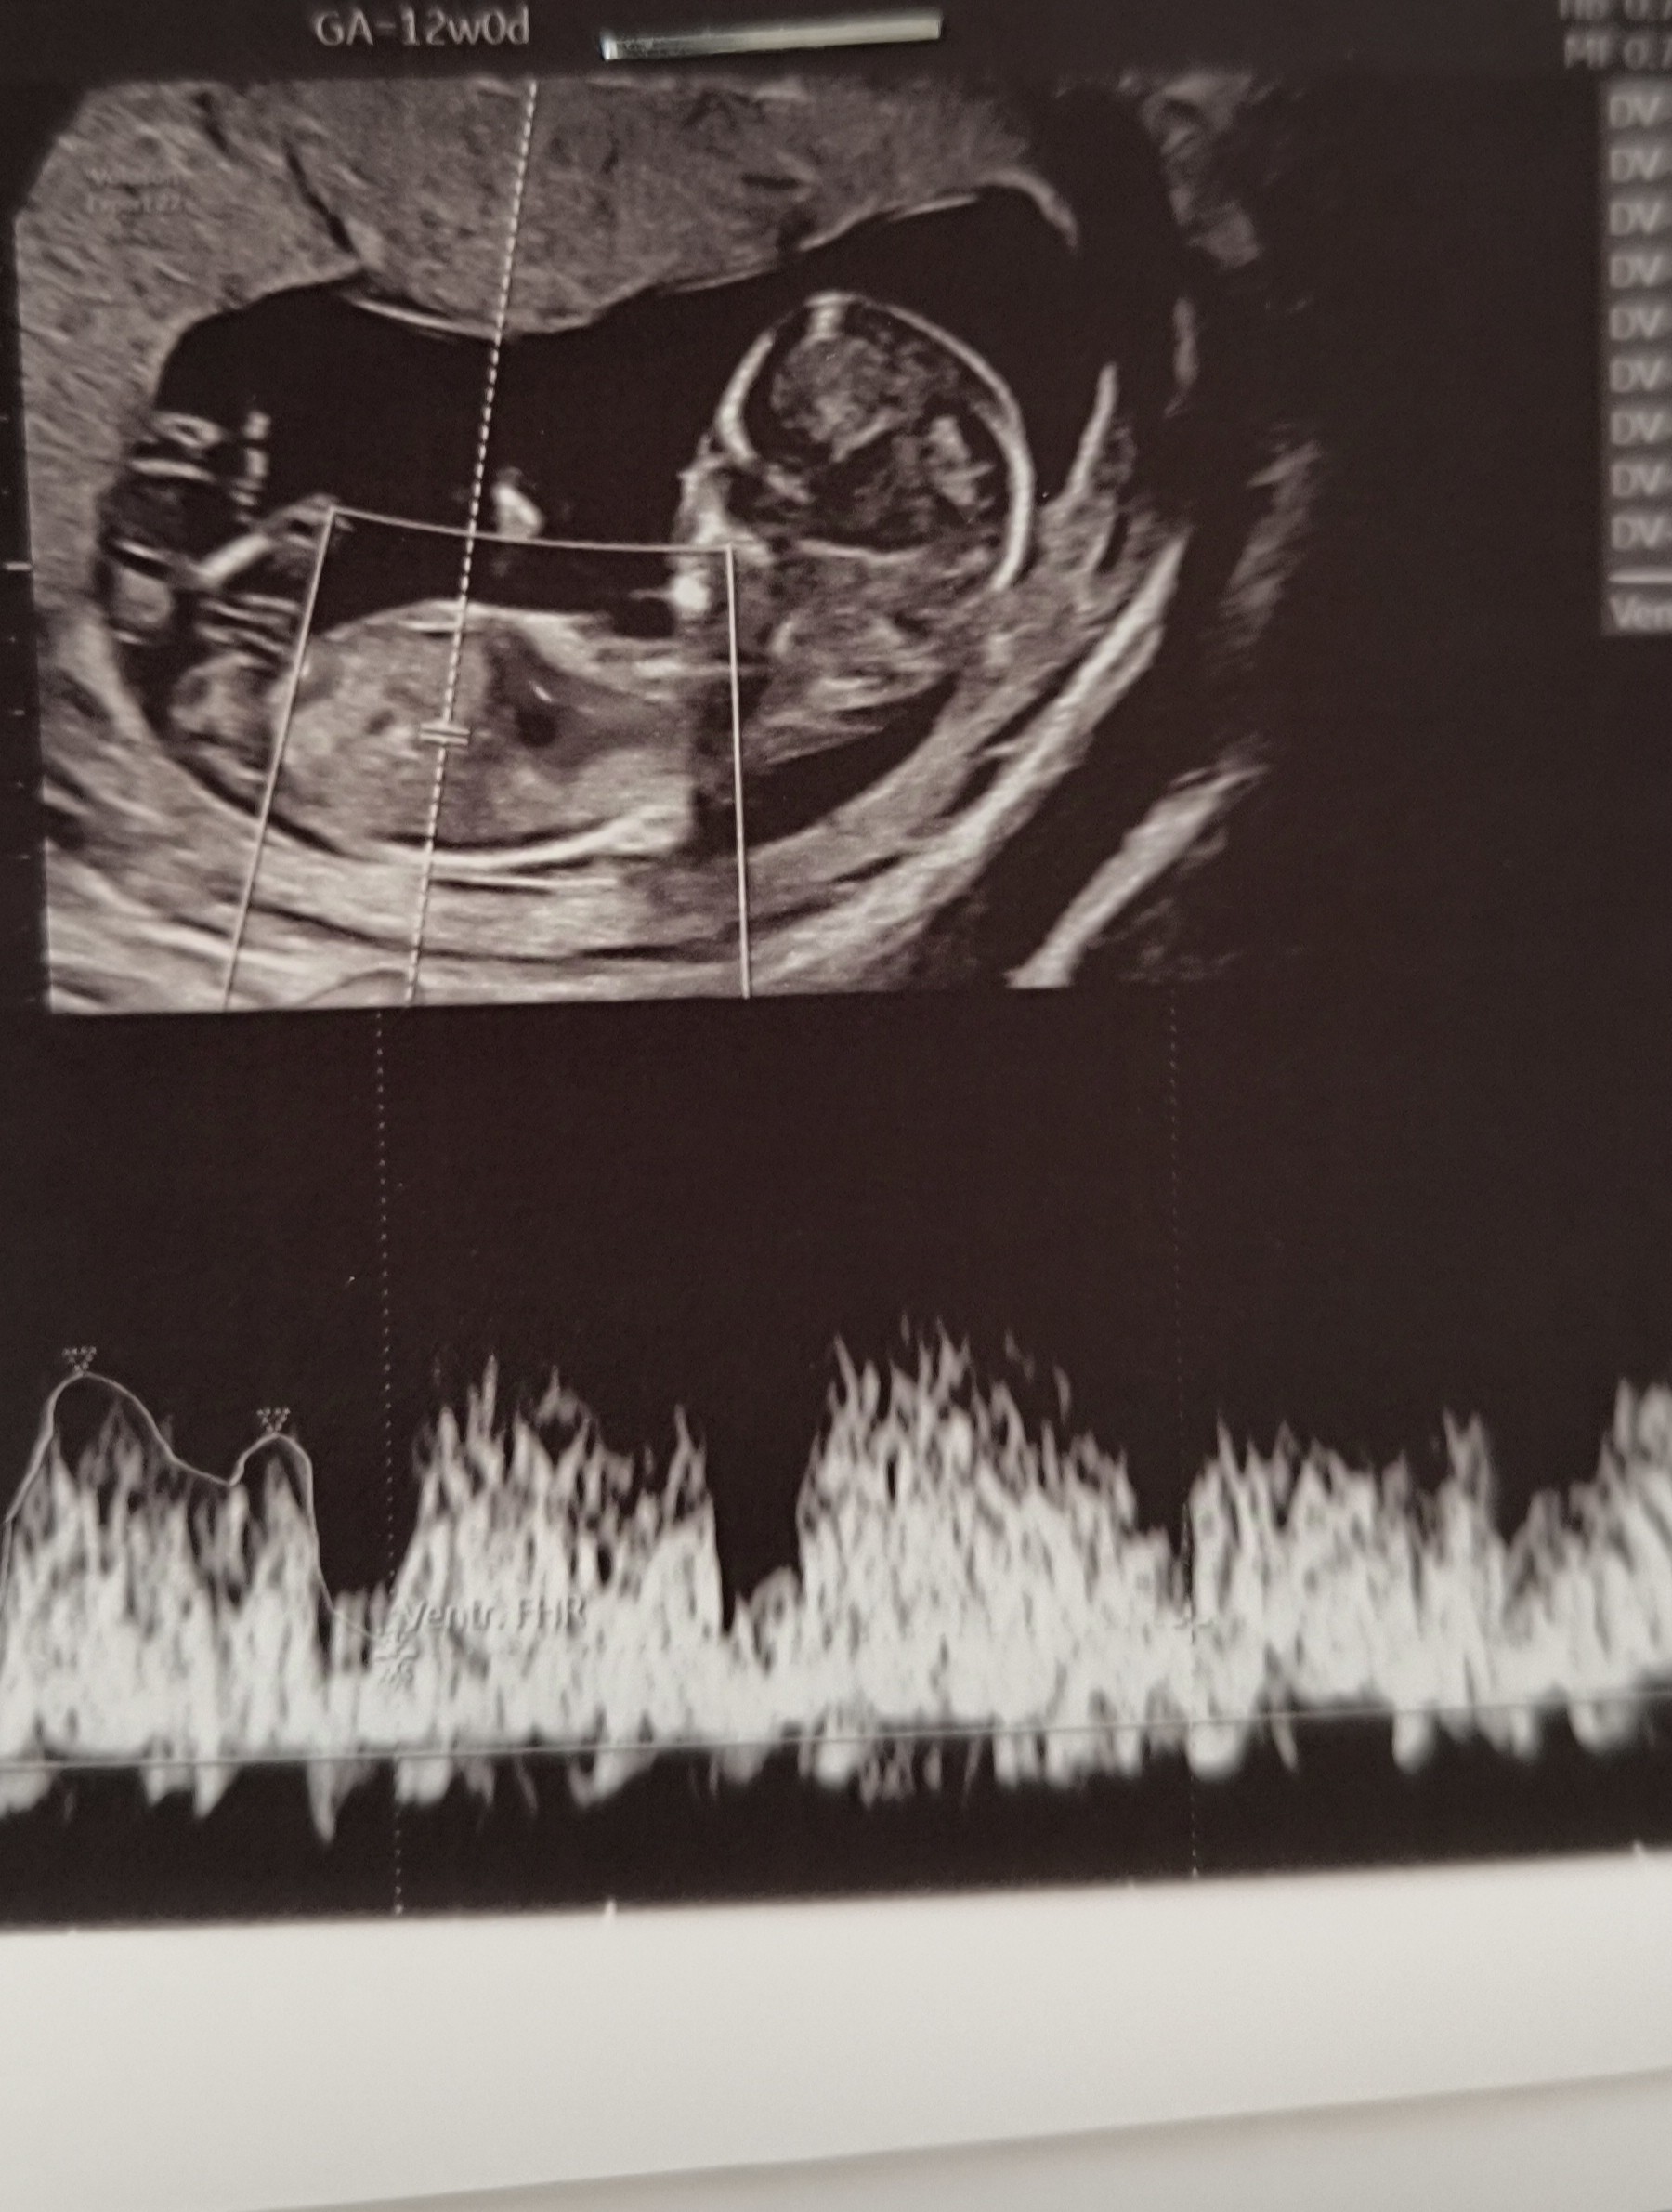

Cześć,

jestem po I prenatalnym. Lekarz rzeczowy, ale tak szybko skończył, że nie zdążyłam się zapytać czy coś widzi 🫣 Jakieś propozycje?

Załączniki

• 20250226_122620.jpg

20250226_122620.jpg

2,2 MB · Wyświetleń: 250